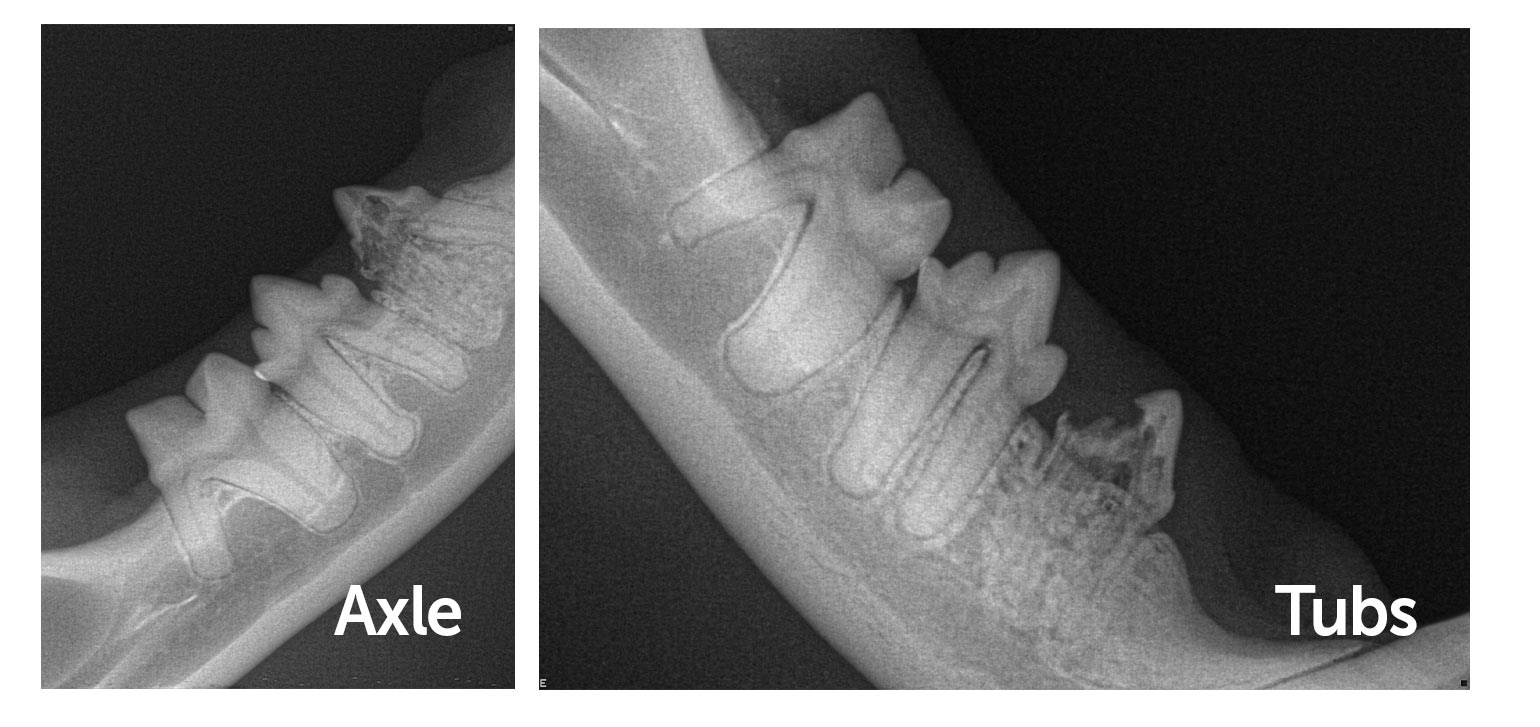

Despite having the same diagnosis, with the help of dental x-rays, we determined that both cats needed a different treatment approach.

Although Axle and Tubs both appeared to have the same issue during their examinations, the real story was revealed once we performed full dental x-rays.

The imaging showed that:

-

Axle’s x-ray showed that some of the root structure remained, meaning we needed to extract the whole tooth

- Tub’s x-ray showed that the root structures had been completely resorbed as well as part of the crown – this meant that we were able to just remove the crown (the part of the tooth above the level of the gum) which is much quicker and easier to do.

Without dental x-rays, it would be impossible to determine the most appropriate treatment for each patient.